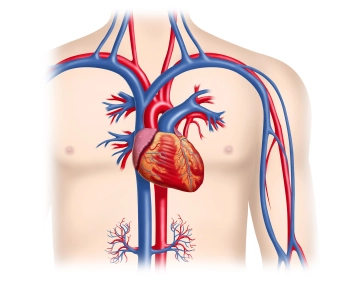

Como órgano hueco muscular, el corazón sirve en el sentido de una bomba de presión-aspiración para el transporte de sangre en la circulación, determinando la dirección del flujo por las válvulas cardíacas. Se encuentra en el mediastino medio, su contorno cónico se proyecta sobre la 2.ª a la 5.ª costilla. La base del corazón se extiende aproximadamente 2 cm por encima del borde esternal derecho, el ápice del corazón limita casi hasta la línea medioclavicular izquierda (MCL). Lateralmente, el corazón está delimitado por las dos hojas pleurales de los lóbulos pulmonares. Dorsalmente, el atrio izquierdo está en contacto directo con el esófago, ventralmente se encuentra la pared torácica con el esternón y caudalmente el corazón se asienta sobre el diafragma, que está firmemente fusionado con el pericardio.

Topografía